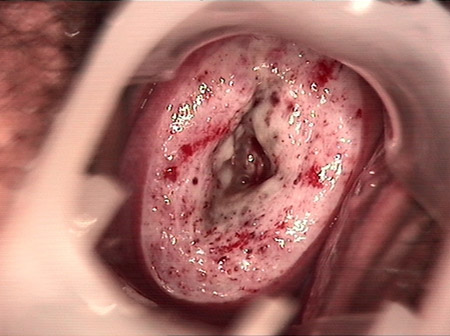

• CIN 2-3 leep術(shù)后CIN 2-3 leep術(shù)后